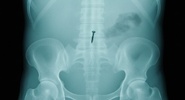

В желудочно-кишечном тракте ребенка при рентгеновском обследовании был обнаружен металлический объект.NEWS.ru